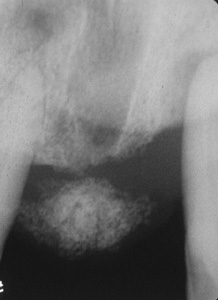

Este fibroma  periférico se proyecta desde la encía y se muestra enrojecido. Parece un granuloma.

Radiografía de la lesión en la imagen anterior revela la formación de hueso, que no es un hallazgo raro en este tipo de lesión.